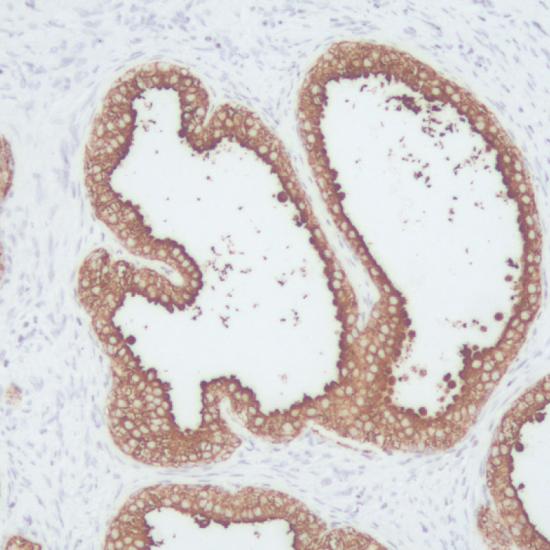

PSA抗體試劑(免疫組織化學(xué)) 閩廈械備20180110號

細(xì)胞漿

前列腺癌

前列腺特異抗原(PSA)是一種分子量為32kD的單鏈糖蛋白,由前列腺上皮細(xì)胞分泌產(chǎn)生,它是一種酷似糜蛋白酶的絲氨酸蛋白酶。PSA具有組織特異性,只存在于人前列腺腺泡及導(dǎo)管上皮細(xì)胞胞漿中,不表達(dá)于其它細(xì)胞。但它并無腫瘤特異性,前列腺炎、良性前列腺增生和前列腺癌均有表達(dá)。